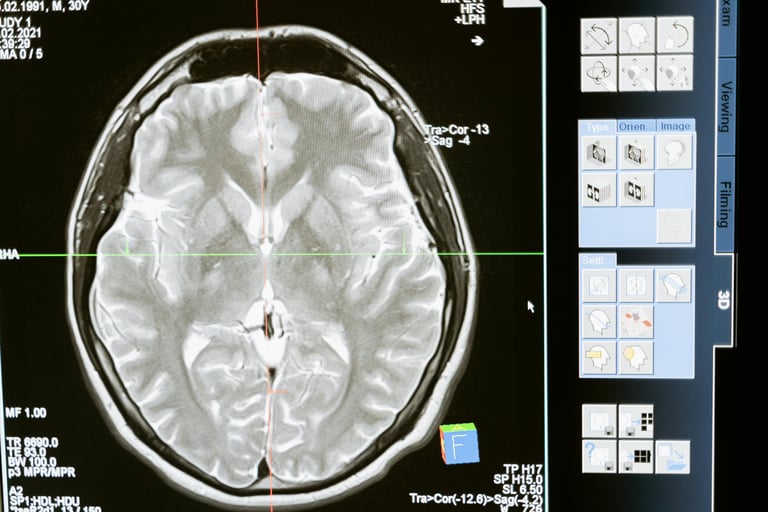

Dowody z obrazowania mózgu w zespole Gilberta

Szczególnie interesujące badanie z Japonii wykorzystało spektroskopię rezonansu magnetycznego (MRS) do analizy chemii mózgu u osób z zespołem Gilberta.

Badacze stwierdzili obniżony poziom mio-inozytolu, markera silnie związanego ze zdrowiem komórek glejowych, zwłaszcza astrocytów.

To subtelne odkrycie — ale bardzo znaczące.